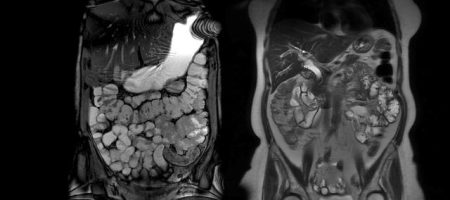

Tüm Vücut MR Nedir? Tüm vücut MR, manyetik rezonans görüntüleme yöntemi ile vücudun baştan ayağa kadar ayrıntılı bir şekilde incelenmesidir. Bu yöntem sayesinde beyin, omurga, boyun, göğüs, karın, pelvis, kas ve iskelet sistemi organları tek bir tetkik ile görüntülenebilir. Amaç, hastalıkların erken dönemde tespit edilmesi ve tedavi planının doğru şekilde yapılabilmesidir. Kanser taramaları, metastaz araştırmaları, […]